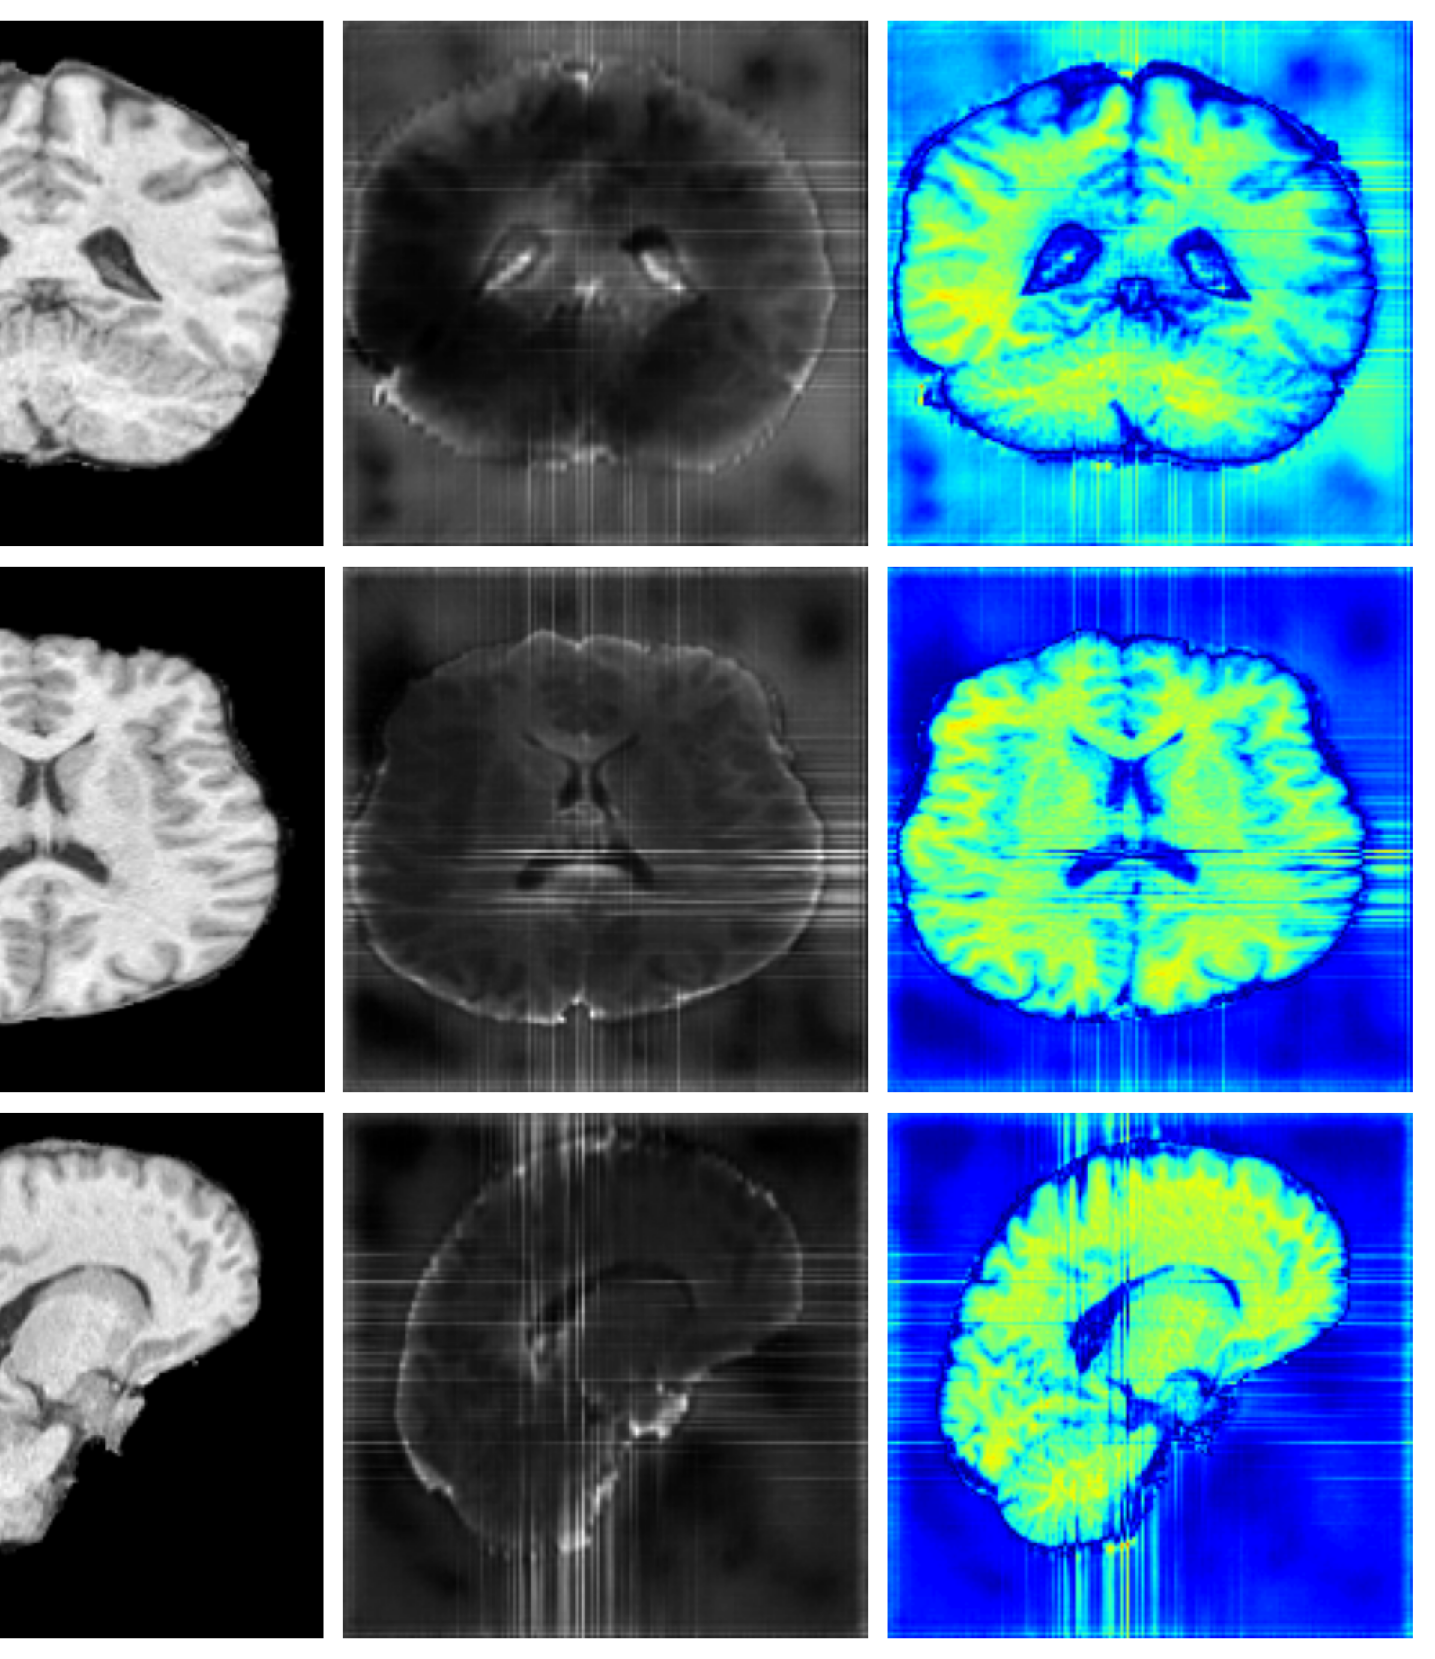

4.2 Image restoration results

IQM values comparing generated to ground-truth high-resolution scans are shown in Table 2. Our method outperforms baselines across several metrics, achieving the highest, or joint highest, rank for all datasets. Data-driven methods, LoHiResGAN, Res-SRDiff and Di-Fusion, fail to generalise to these cohorts, as illustrated by their poor performance. SynthSR, although outperforming competitively on some IQMs (and outperforming our method in VIF for T1w Clinical), is restricted to predicting T1w intensities. UniRes is often a close performing baseline, which is expected given that it also models image restoration explicitly with a forward model similar to ours. UniRes outperforms our method in some VIF values, whereas our method consistently achieves second best performance in this metric. For all other IQMs across all datasets, our method achieves the best performance, in some instances by quite considerable margins.

Qualitative T1w results are shown in Figure 2, with further examples for other modalities in Appendix A.8. LoHiResGAN and Res-SRDiff produce unrealistic images with severe artifacts, likely arising from bias fields, sharp intensity artifacts, and other noise not present during training. UniRes generates oversmoothed images, likely due to its TV prior and its reliance on information from multiple input modalities, whereas we apply it unimodally. Di-Fusion shows less pronounced but still notably blurry, voxelated reconstructions which lack the fine-grained details generate by our method. This is likely, in part, due to our use of synthetic rather than real noisy training data, which the method was designed for. As such data is scarce, and in our case unavailable, this requirement represents a significant limitation of Di-Fusion. SynthSR, whilst not as well as our method, does preserve key anatomical structures. However, our difference maps show reduced contrast, further supporting the strong quantitative results shown in Table 2.

For both the Clinical and Low-field datasets, low-resolution images are skull-stripped and normalized to [-1, 1]. The alignment to MNI space is required by forward model given in Equation 11 and is achieved by recomputing the affine transformation through centroid alignment of anatomical labels from SynthSeg Billot2023 segmentations with the corresponding atlas centroids. Example low-resolution images are shown in Figure 6.

A.8 Additional qualitative restoration results

Additional qualitative results for the Clinical dataset are given in Figures 7, 8 and 9, and for the Low-field dataset in Figures 10 and 11.